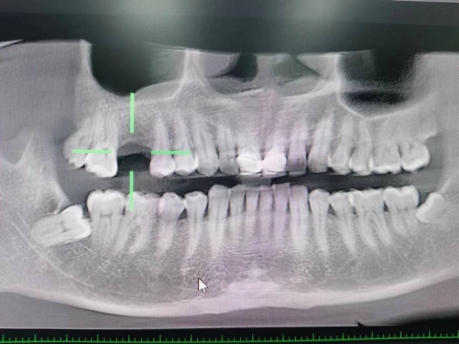

武先生术前检查图

据了解,53岁的武先生,因右上后牙缺失多年,缺失的牙齿给他造成了不小的烦恼,影响到了正常咀嚼功能。在了解到公司口腔科能开展种植牙手术以后,武先生前来咨询,经过仔细全面的口腔检查和CT检查、检验等检查,武先生符合种植牙条件,决定实施右上后牙区种植牙的修复方案。本次手术由陈河林博士主刀,黄魁副主任做助手,在口腔中心成功完成该院首例种植牙手术,手术历时约30分钟,术中微创操作,患者全程无痛,术后无不良反应,整个诊疗过程舒适、安全、精准,经术后CT检查种植体位置精确。